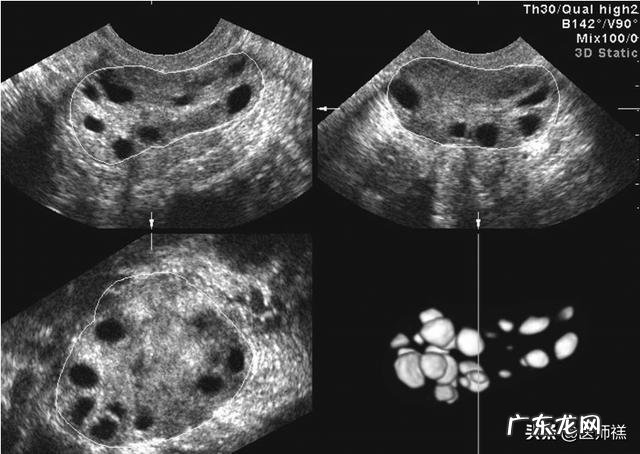

卵巢综合中是一种内分泌疾病,多见于青春期 。主要是由于在青春期阶段因为患者体内雄激素分泌过高导致持续无排卵和卵巢多囊改变的特征 。这种变化通常会使女性两侧的卵巢发生均匀性改变,因为雄激素的原因要比正常同龄阶段女性的卵巢大2-5倍 。卵巢通常表现为切面增厚,会出现白膜样的改变 。在临床B超检查种上多会出现超过12个直径约为2-9mm囊性卵泡,变现为无回声,呈现出项链状的排布,但是这些不成熟的卵泡通常呈现闭锁状态,并没有成熟的卵泡生成或排卵迹象 。